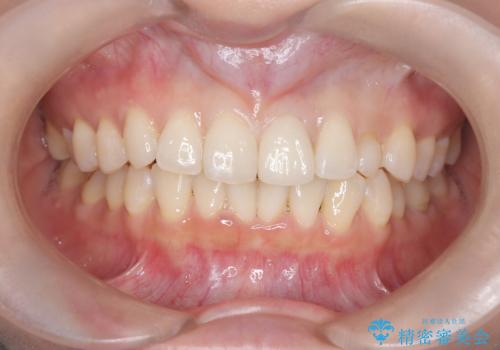

- 20代女性

- 以前に前歯を折れた時、コンポジットレジンで修復したが、変色してきたことを主訴に来院されました。

今回は、セラミッククラウンによる修復を希望され、治療を行っています。